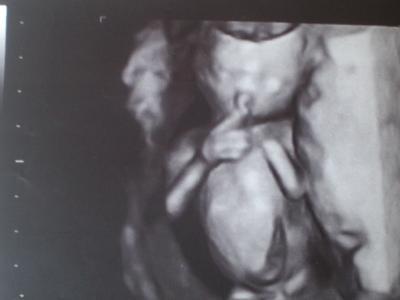

So, ich versuche mal das US bild hochzuladen. Ich habe es mit der Kamera fotografiert, ich hoffe es ist nicht zu verschwommen. Es ist auf jeden Fall ein 3D Bild, wo mein Baby gerade am Finger nuckeln ist

Hat doch super geklappt Mein Gott, sieht des süß aus, beim nuckeln erwischt lg